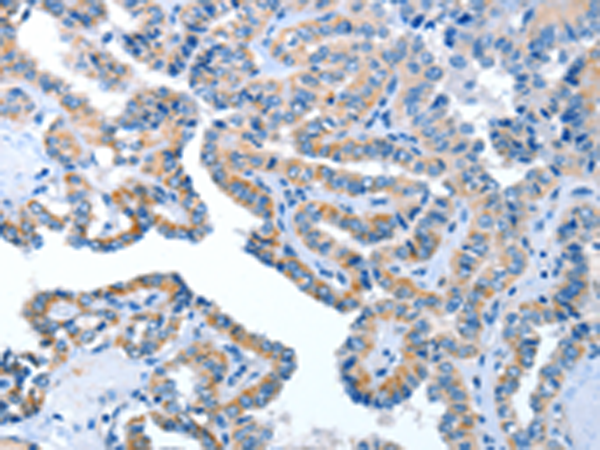

分类: 科研抗体货号: P07817别名: CDG1G; ECM39; hALG12; PP14673应用: IHC反应种属: Human, Mouse